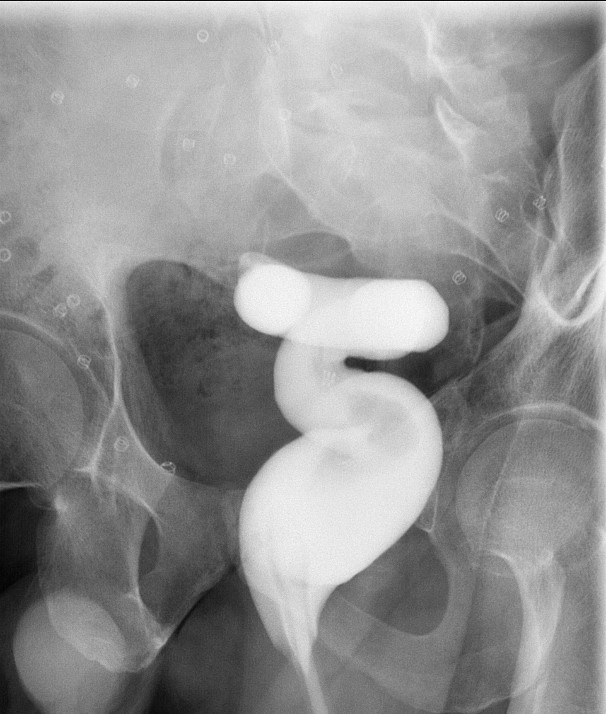

- Once the barium has reached the small bowel, you will go into the room and obtain spot images of the contrast material filled small bowel.

- Obtain images of the terminal ileum and the ileocecal valve filled with contrast material

(key image 6)

(key image 7)

(key image 8)

(key image 9)

(key image 10).

- Obtain spot images of the remainder of the small bowel

(key image 11)

(key image 12)

(key image 13)

(key image 14).

- Obtain images of all four quadrants. Use the compression paddle to separate loops of small bowel from each other.

- Evaluate for tethering of small bowel to any other structures.

- Observe for small bowel peristalsis.